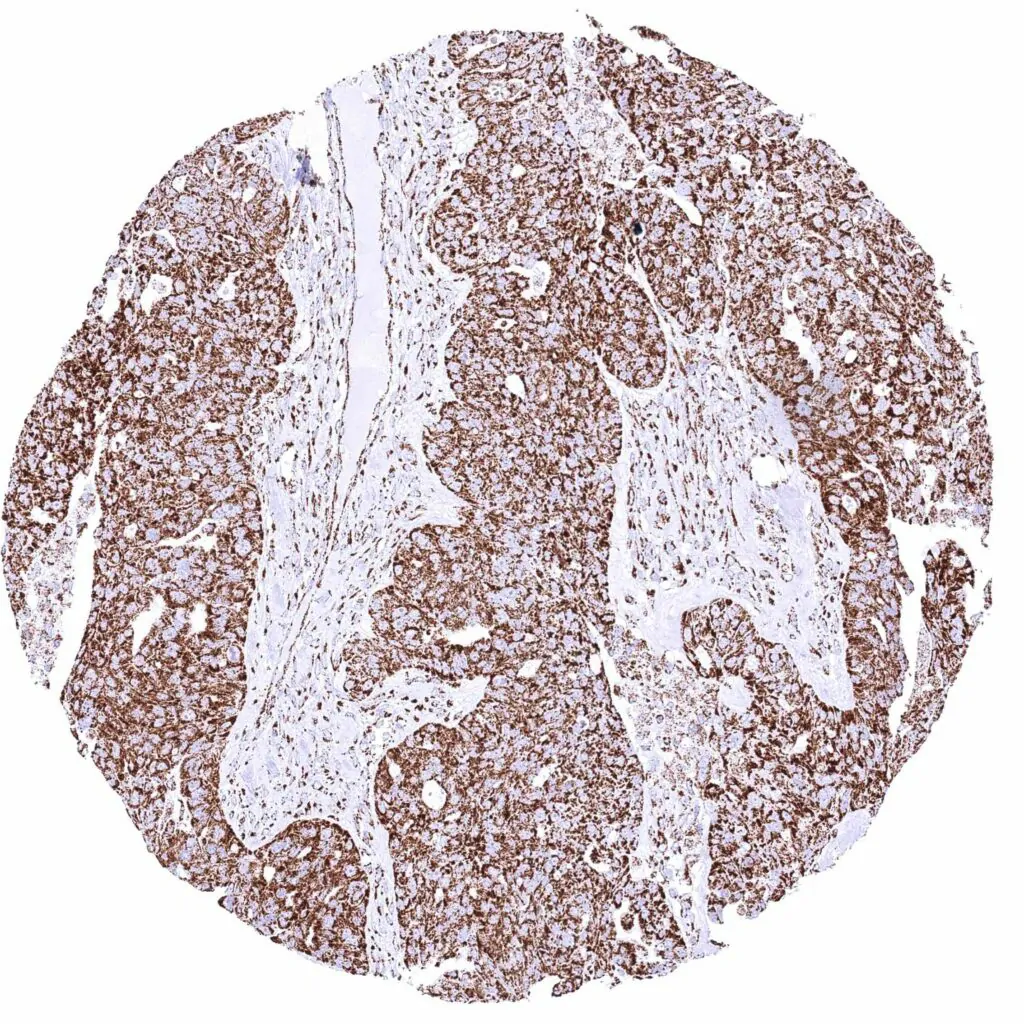

Prostate – Adenocarcinoma (Gleason 5+5=10) with intense cytoplasmic ATP5J positivity of all tumor cells.